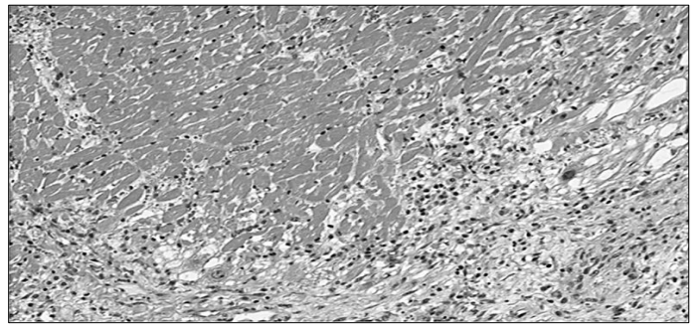

A imagem microscópica abaixo representa o corte histológico de uma lesão localizada na parede anterior do ventrículo esquerdo, encontrada

no exame de necrópsia de um paciente de 48 anos de idade, sexo masculino, encontrado em óbito no seu domicílio: